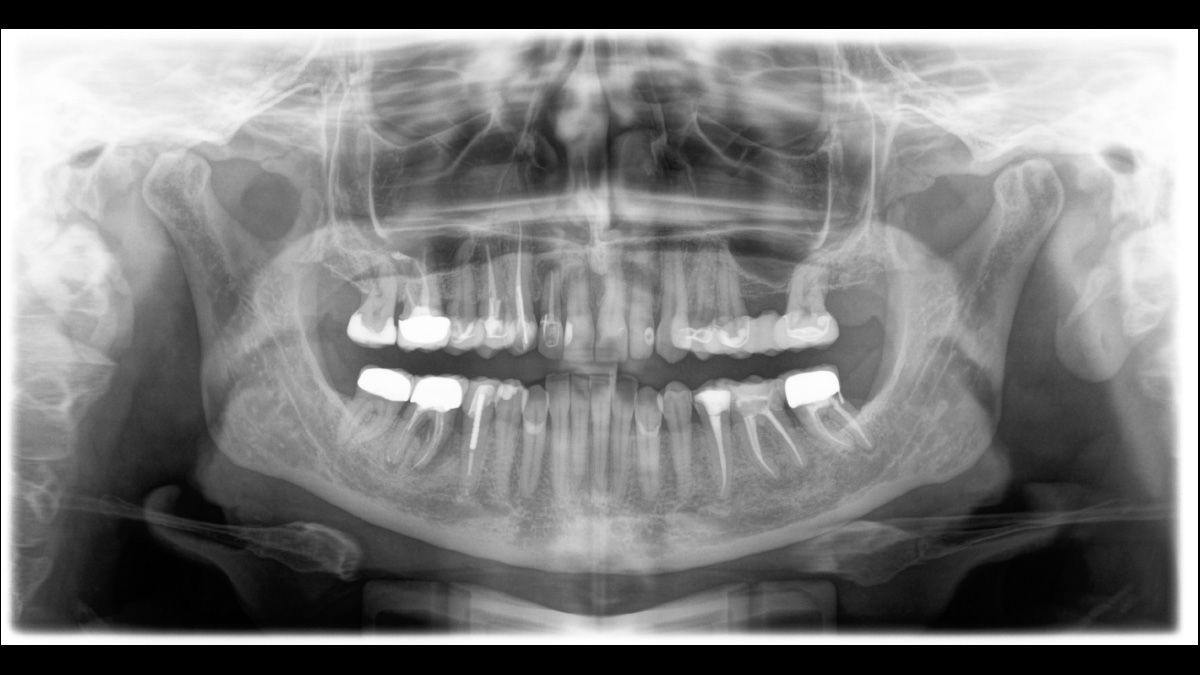

The right focus is crucial for excellent panoramic radiographs. With the autofocus function you will automatically receive an image with the best possible sharpness in focus. The Orthophos S creates several thousand individual images in one revolution and automatically recognizes the areas in which the jaw is optimally positioned. A sharp panoramic image is created from the individual projections – without any manual intermediate steps.